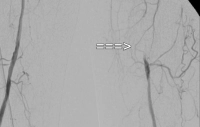

Exemplo de vídeo: TASC C → reconstrução aberta

Estágio IIb de DAP esquerdo (distância de caminhada inferior a 100 m). A DSA pré-operatória mostra:

- uma estenose subtotal da artéria femoral comum

- uma oclusão de segmento longo da artéria femoral superficial no canal adutor

- oclusões parciais das artérias da perna inferior